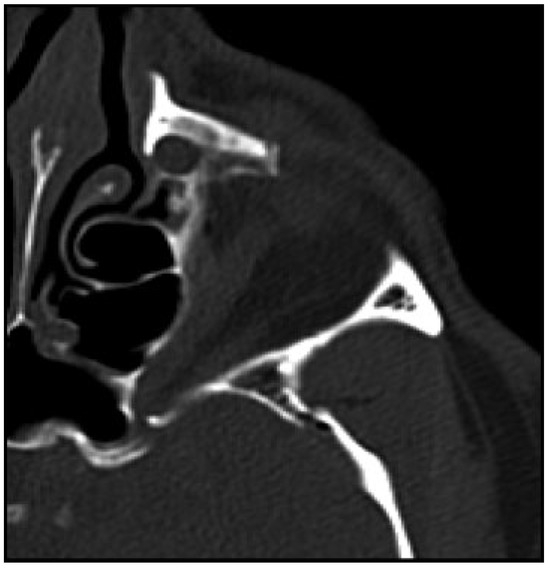

Imaging included a maxillofacial computed tomography (CT) which revealed comminuted fractures of the anterior, posterolateral, and posteromedial walls of the left maxillary sinus with air fluid levels and a hematoma. In addition, fractures of the left orbital roof and lateral and inferior walls were noted. The globes were found to be intact, with no definitive evidence of muscle entrapment. However, disruption of the left superior orbital fissure was found (Figure 3 and Figure 4).

Figure 3. Maxillofacial computed tomography scan:, axial cut, bony window, at the level of the zygomatic arches showing left displaced zygomaticomaxillary complex fracture.